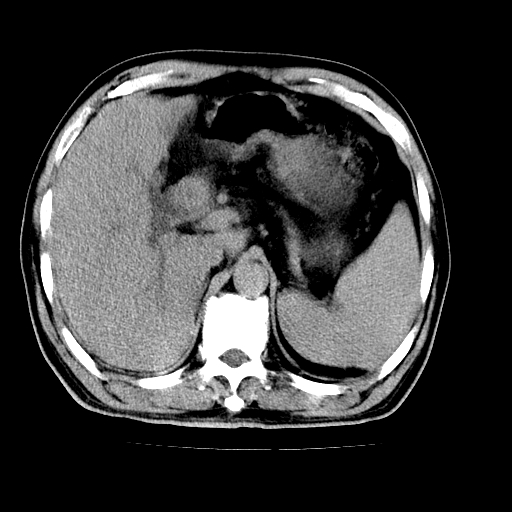

男,66岁,上腹部不适、黄染一周。彩超示:肝左叶占位,肝内胆管扩张,胆总管扩张,胆总管占位?

肝左叶不规则软组织肿块影,边缘不规整邻近肝实质受累分界不清;肝内胆管(左叶)明显扩张成“软藤状”,诊断:肝左叶胆管细胞癌。

肝左叶占位性病变,并胆管扩张,符合胆管细胞癌ct表现,门脉左支受累,左肾囊肿。窗宽太窄了,其他的看不清

左叶胆管细胞癌累及胆总管,门脉左支受侵,慢性胆囊炎胆结石,左肾小囊肿